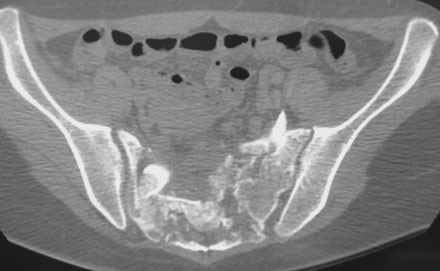

Травма 21.августа 2005г. На девочку в лесу упала береза. Доставлена в ближайшую ЦРБ. При поступлении установлен диагноз: Травматический шок 2-3 ст. Тупая травма живота. Забрюшинная гематома. Перелом костей таза с нарушением целостности тазового кольца. Перелом лонной и седалищной костей справа. Перелом поперечных отростков L3 - L5. Разрыв КПС справа. При поступлении выполнена диагностическая лапароскопия — выявлена обширная забрюшинная гематома. Было наложено скелетное вытяжение за бугристости обеих б/берцовых костей, больная уложена в гамак. Через неделю скелетное вытяжение демонтировано, гамак снят. Девочка уложена в положение «лягушки». Контрольные рентгенограммы через 4 недели после травмы. Заподозрен перелом дужки L5. Больная 26 сентября 2005 г. переведена в областную больницу в отделение детской ортопедии. При поступлении в локальном статусе: пальпация и перкуссия остистых и поперечных отростков L4-5 болезненная. Пальпация костей таза б/болезненная. С-м натяжения слабо положителен. Осевая нагрузка положительная. Движения в т/б суставах ограничены, болезненны. C-м прилипшей пятки отрицательный. C-м Ларрея и Варнейля отрицательный. Периферическая гемодинамика не нарушена.Неврологический статус: вторичная двусторонняя радикулопатия L5-S1. 29 сентября произведена компьютерная томография позвоночника и таза.

Судя по томограммам, радикулопатия может быть из-за компресии "конского хвоста" смещенным крестцовым позвонком, это хорошо видно на втором слева снимке. Если этот сегмент будет нестабилен и будет сохраняться неврологическая симптоматика, придется оперировать. Если неврологическая симптоматика уйдет и перелом стабилизируется, то можно обойтись без операции.